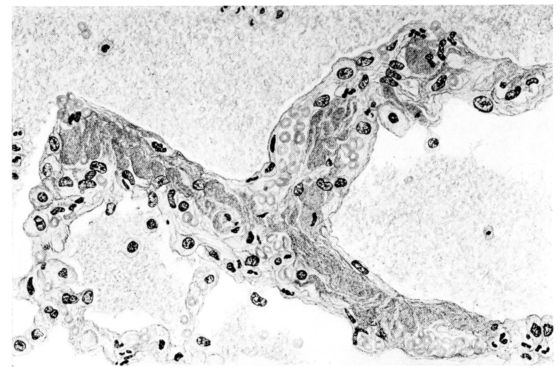

FIG. IV. AUTOPSY NO. 205. CONGESTION AND EDEMA OF THE SUBMUCOSA AND REGENERATION OF THE TRACHEAL EPITHELIUM.

The changes are less marked, perhaps, in the trachea than in its finer ramifications. The mucosa is constantly more or less destroyed and large areas, usually focal, are entirely devoid of their epithelial covering. This is replaced by a sparse exudate, composed largely of red blood cells, mucus, a small amount of fibrin, and nuclear fragments (Fig. II). It may dip into the submucosa for a short distance, but usually these indentures are associated with the ducts of the mucous glands into which the inflammatory reaction extends. A more striking feature than the exudate, however, is the edema and the congestion of the submucosa. The loose areolar tissue of the submucosa is spread widely apart, and throughout it distended blood vessels are very conspicuous. Occasionally such a vessel is broken and actual hemorrhage appears in the submucosa. Occasionally, too, the inflammation extends down the duct to the mucous gland itself, and here, also, aplastic inflammatory reaction is evident, inasmuch as the acini now stain intensely red with the cells undifferentiated from each other and specked here and there by broken remains of the dead nuclei (Fig. III). After the disease has continued for a short period, even at the end of five or six days, some regeneration of the epithelial lining may be seen (3) (Fig. IV). But despite this, the acute picture persists, and there goes on, side by side, an attempted repair characterized by epithelial regeneration and the same evidence of acute change. Since the lesion is essentially a superficial one, scars or contractures of any extent are not encountered in the trachea, even in examples of the disease that have ended fatally only after many weeks.[4]